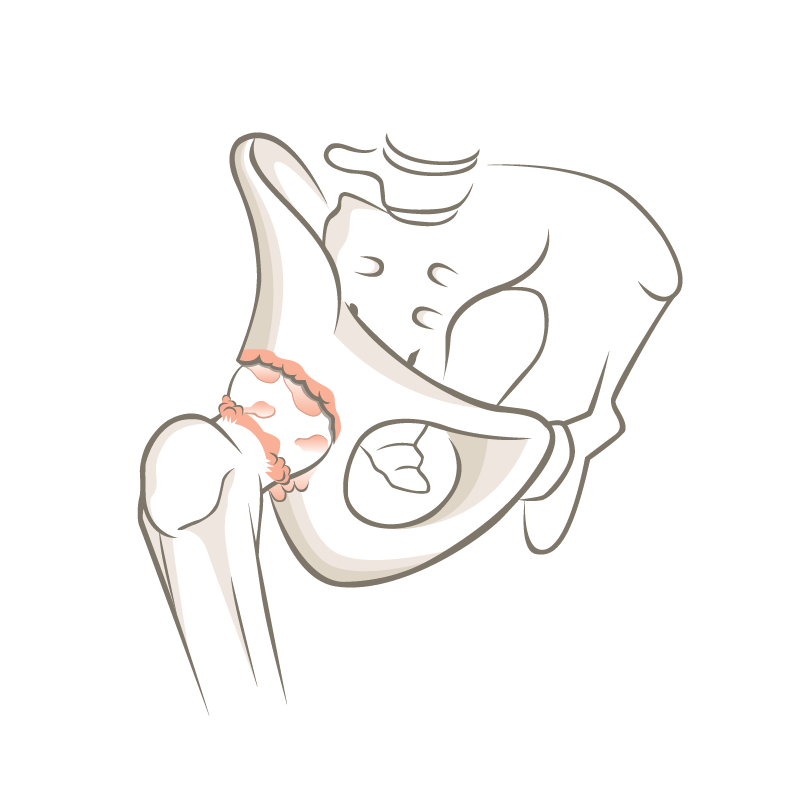

Aufgrund der Beschaffenheit des Materials entsteht praktisch kein Materialabrieb, was sich sehr günstig auf die Langlebigkeit der Prothese auswirkt. Insbesondere für sportliche Patienten ist dies ein Lichtblick für die operative Behandlung einer Hüftarthrose.

Dr. Philipp Neidenbach berichtet über die Entwicklung der Endoprothetik des Hüfgelenkes. Die Hüfttotalendoprothese revolutionierte seit den 1960er-Jahren die Behandlung der schweren Hüftarthrose, so dass die Implantation der Hüftprothese bereits 2007 als «Operation des Jahrhunderts» gefeiert wurde. Die stete Weiterentwicklung der Operationstechniken und Materialien der Implantate hat dazu geführt, dass Patienten schmerzfrei mobil sein können.